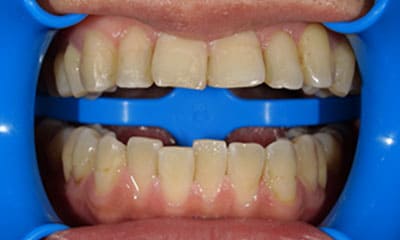

症例

+

藤沢デンタルオフィスのホワイトニング術前 藤沢デンタルオフィスのホワイトニング術後

術前

術後